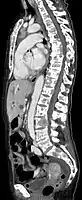

- Comparaison scanner/IRM pour des métastases ostéolytique d'un cancer du sein dans la colonne vertébrale

Scanner sagittal reconstruit, représentation dans la fenêtre osseuse. Comme la patiente avait des métastases dans toutes les régions du corps, elle ne pouvait pas lever les bras pour l'examen, ce pourquoi les mains sont présentées.

Scanner sagittale, parties molles. Outre les métastases dans la colonne vertébrale, qui envahissent en partie le canal médullaire vers l'arrière, métastases aussi dans le sternum. Plus des métastases dans le foie.

IRM natif avec pondération T1.

IRM sagittal natif avec pondération T1. On voit clairement l’extension jusqu'aux lames vertébrales.